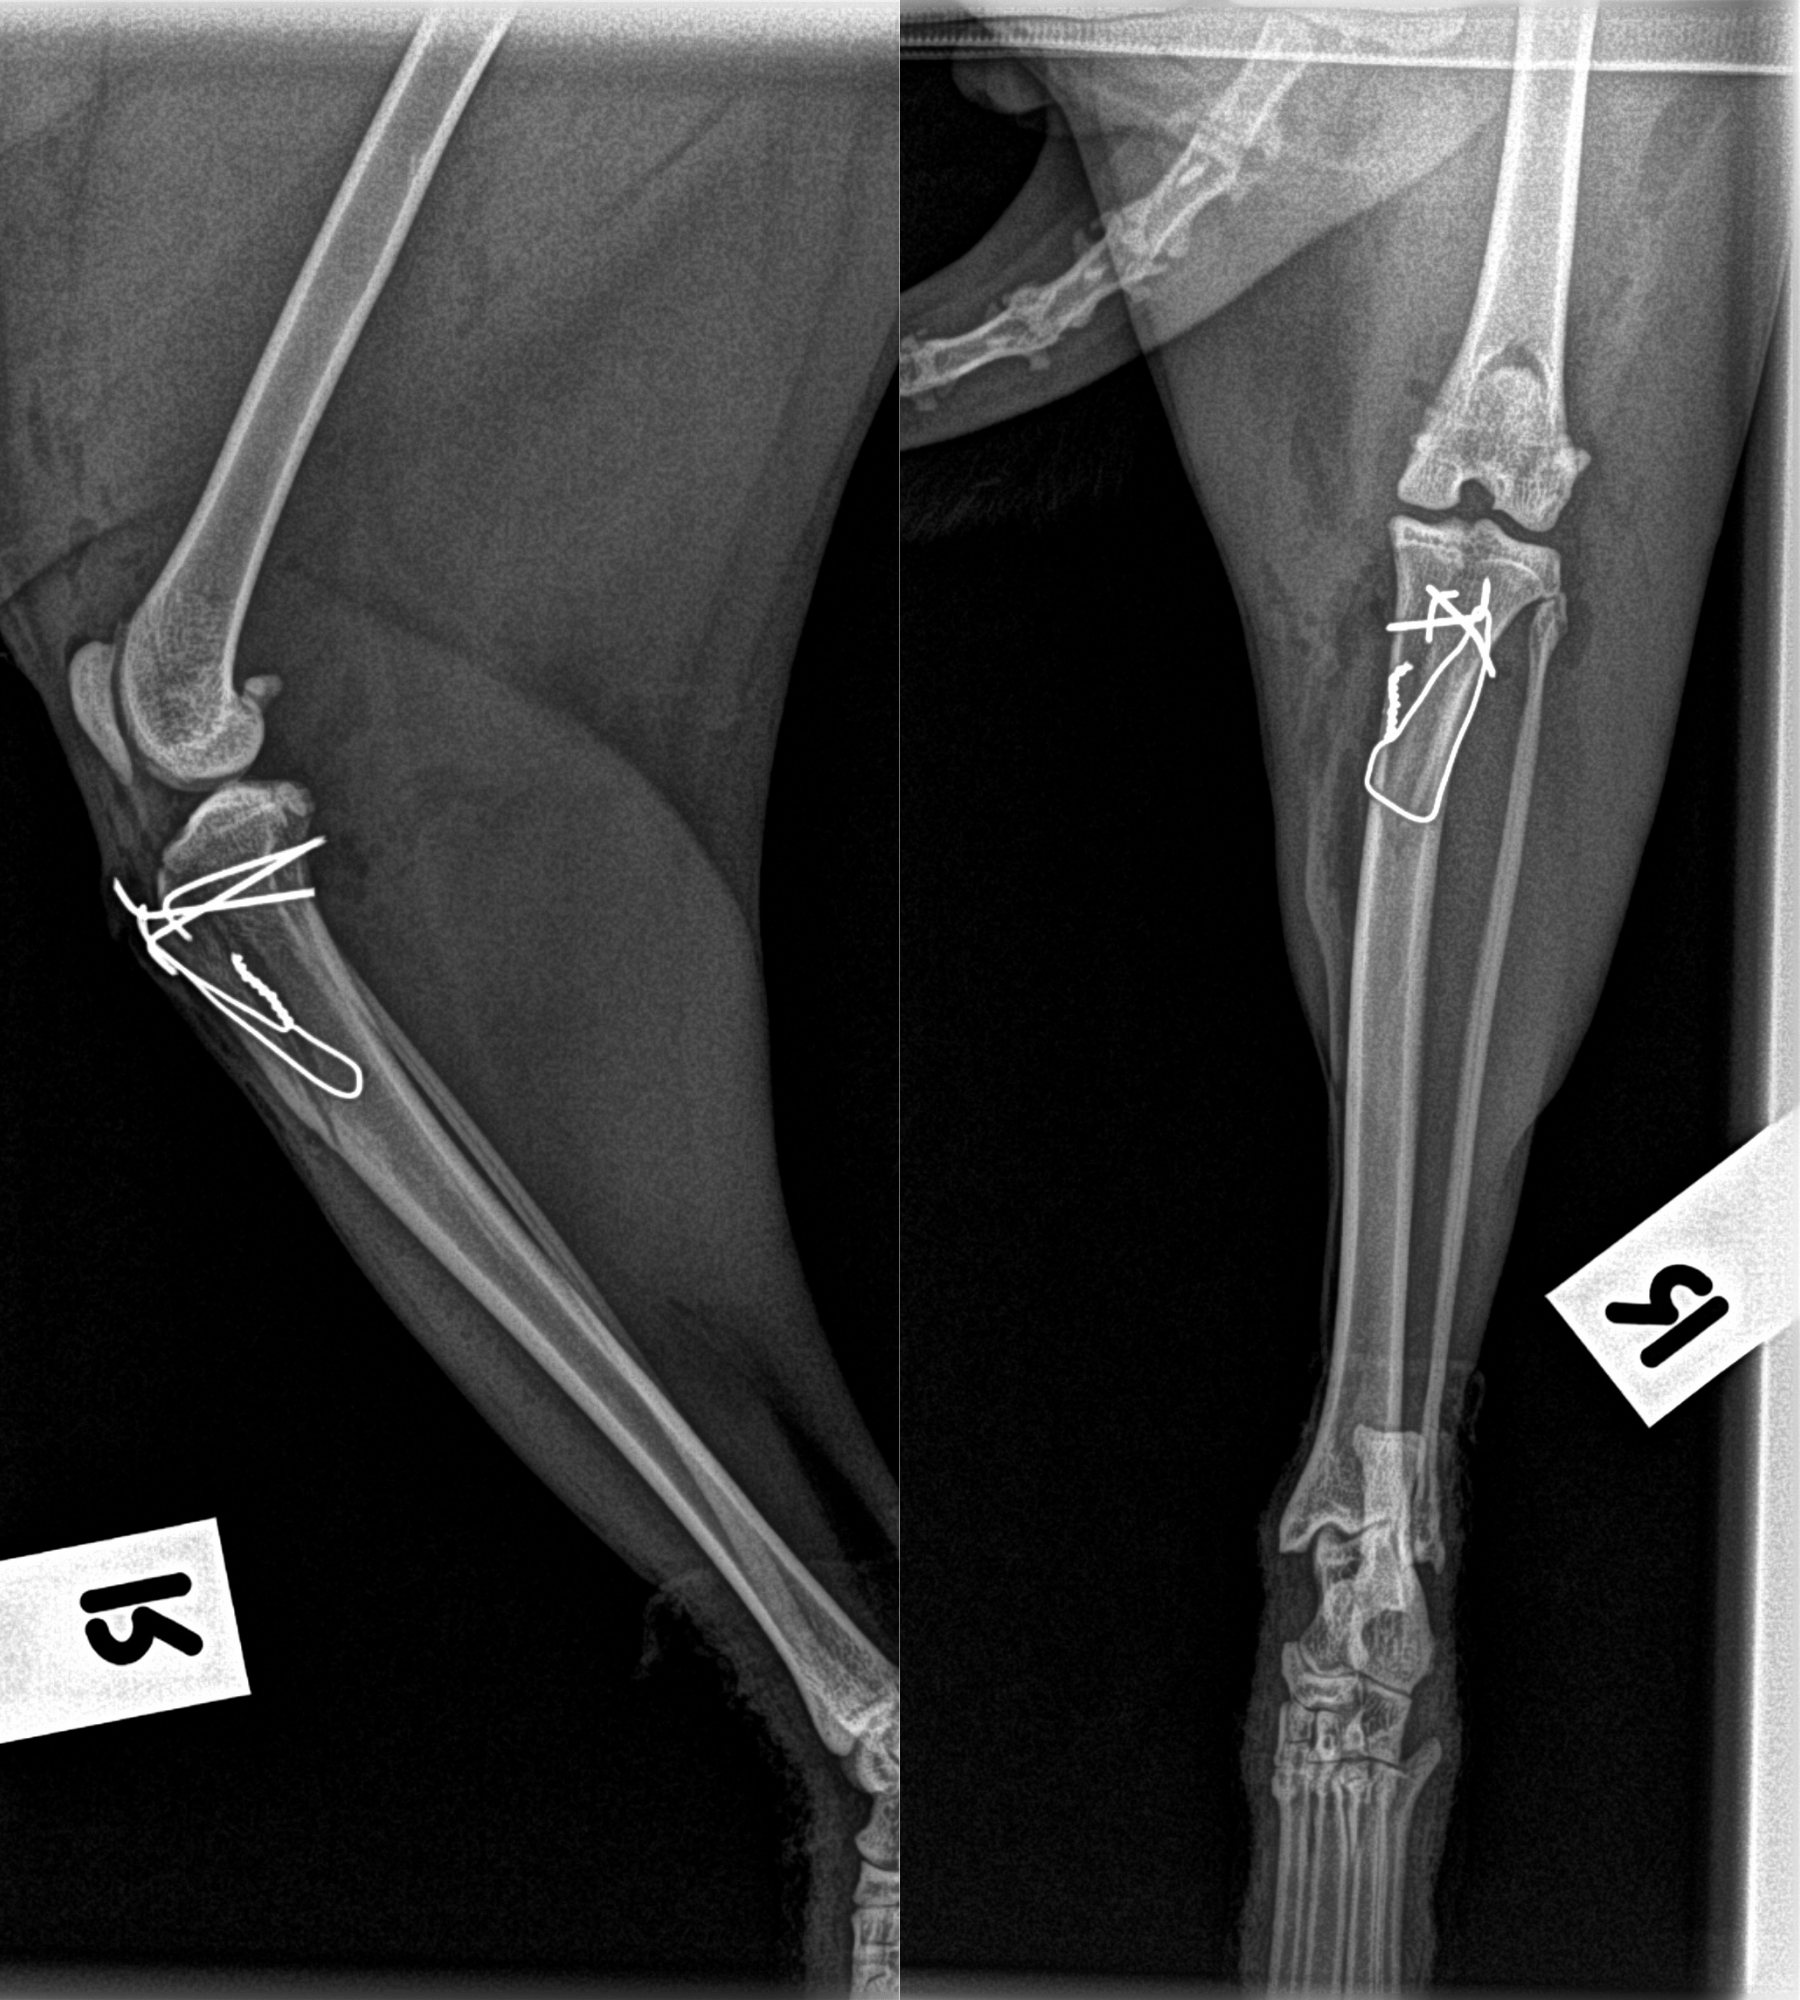

This wasnât a simple âput it backâ job it required a multi-step orthopaedic approach:

đ§ What was done during surgery:

The result?

âď¸ Smooth tracking of the patella

âď¸ Full range of motion restored during surgery